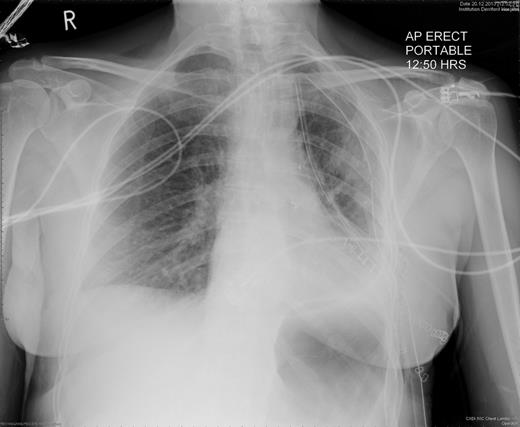

A 57-year-old woman with a left upper lobe mass was referred to our institution for lung resection. Preoperative computed tomography (CT) and positron emission tomography were consistent with lung cancer. Pulmonary function tests revealed a forced expiratory volume in 1 s of 1.64 l (64% predicted), forced vital capacity of 3.1 l (104% predicted) and TLCO of 97% predicted. The patient underwent an uncomplicated left upper lobectomy through open thoracotomy. The fissures were complete, and the inferior pulmonary ligament was mobilized in part. A systematic nodal dissection was performed. She was extubated immediately after surgery and was transferred to the ward as per routine practice. Post-operative chest radiograph revealed satisfactory expansion of the left lower lobe (Fig. 1). On the first operative day, the patient remained haemodynamically stable, without systemic upset, but developed atrial fibrillation with tachycardia. Chest X-ray demonstrated complete opacification of the left hemithorax with normal position of the left hemidiaphragm (Fig. 2). Urgent rigid bronchoscopy revealed narrowed left lower lobe bronchial orifice and the bronchoscope could not pass through. The left upper lobe bronchial stump was intact. Immediate exploratory thoracotomy was performed. At surgery, the left lower lobe had undergone a 180° anti-clockwise torsion at its brochovascular pedicle. The lung parenchyma was very fragile and haemorrhagic, compatible with early venous infarction, hard with a dark reddish surface. Torsion of the lower lobe was corrected and lower lobe was sutured to pericardium, in order to further investigate the anatomy, and determine whether completion pneumonectomy could be avoided. Her AF resolved with restitution of the lobe. A minitracheostomy was inserted prophylactically. However, over the course of the first few post-operative hours, the patient became progressively more hypoxic and tachypnoeic. CT was performed, demonstrating acute obstruction with possible angulation of main pulmonary artery and complete obstruction of left main bronchus (Fig. 3), reported as demonstrating recurrent torsion. The patient returned to theatre for a third time, and at throacotomy, the lobe was found to be in its normal position, but there was now further evidence of infarction, and completion pnuemonectomy was performed. Histological examination confirmed haemorrhagic congestion throughout the left lower lobe parenchyma. Post-operative course was uneventful and patient was discharged home on Day 7.

Chest radiography on the first post-operative day shows left-sided consolidation with normal left hemidiaphragm position.